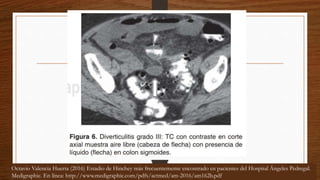

Octavio Valencia Huerta (2016) Estadio de Hinchey más frecuentemente encontrado en pacientes del Hospital Ángeles Pedregal.

Medigraphic. En línea: http://www.medigraphic.com/pdfs/actmed/am-2016/am162b.pdf